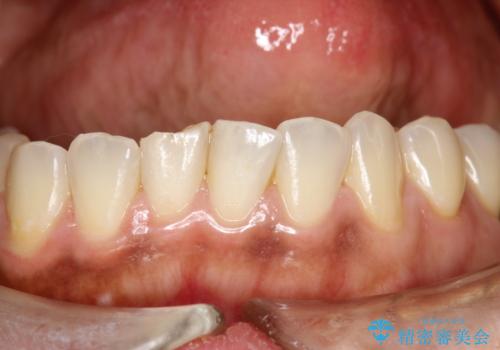

- 現在妊娠5か月で、安定期に入ったため、出産前にお口のクリーニング希望とのことでした。PMTC60分コースを行いました。

個人差がありますが、 つわりがなく妊娠前とかわらずに過ごしている方でしたら初期でもお口の中のクリーニングする事は可能です。

妊娠初期は、つわりなどの影響でしっかり磨くことができず、妊娠性歯肉炎や妊娠性歯周炎を起こしやすくなることがあります。

セルフケアだけでは、歯周病を治したり予防したりすることは困難です。

歯科医院で専門的なにクリーニングを行い、歯石除去や細菌に汚染された歯根面の掃除が大切です。